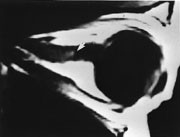

De fleste ansiktsskader med brudd er assosiert med orbitaskader, derfor bør undersøkelsen kompletteres med radiologisk undersøkelse av orbita hos alle pasienter med slik skade (12). Ved ”blow-out-fraktur” oppstår en diskontinuitet av orbitagulvet, som kan føre til herniering av orbitainnhold, så vel fett som muskler. CT-rekonstruksjon med 5 mm tykke snitt er ikke adekvat, men man kan i dag benytte tynnere snitt og rekonstruksjoner (fig 10). Det kan være vanskelig å skille isodens muskel fra ødem og blod i det hernierte fettet. I slike tilfeller er MR å foretrekke.

Orbital apeks- og optikuskanalfraktur kan forekomme enten isolert eller sammen med andre komplekse brudd. Skade i dette området er kritisk, grunnet nær relasjon til synsnerven. I tillegg til direkte overskjæring kan trykk fra beinfragmenter, hevelse eller blødning skade nerven. Tynn snittføring med multiplanare vurderinger av spiral-CT-bildene er nødvendig for å kunne stille riktig diagnose.

Skader som gir mistanke om brudd i orbitaveggen bør undersøkes med CT. Til fremstilling av orbitataket og gulvet bør CT utføres også i koronal plan.